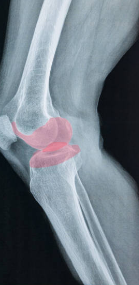

5) 무릎이 붓는다 (관절에 물이 찬다)

무릎 연골이 손상되면 관절 안에 염증이 생기면서 관절액이 늘어나요.

그럼 무릎이 부어 보이거나, 무릎 앞쪽이 빵빵해지고, 구부리기가 힘들어지기도 해요.

특히 활동 후 붓는다면 무릎 내부에 자극이 반복되고 있다는 신호예요.

5) O다리, X다리 같은 다리 정렬 문제

다리 정렬이 틀어져 있으면 체중이 무릎 안쪽 또는 바깥쪽으로 쏠리게 돼요.

그 쏠리는 부위는 연골이 더 빨리 닳을 수밖에 없지요.